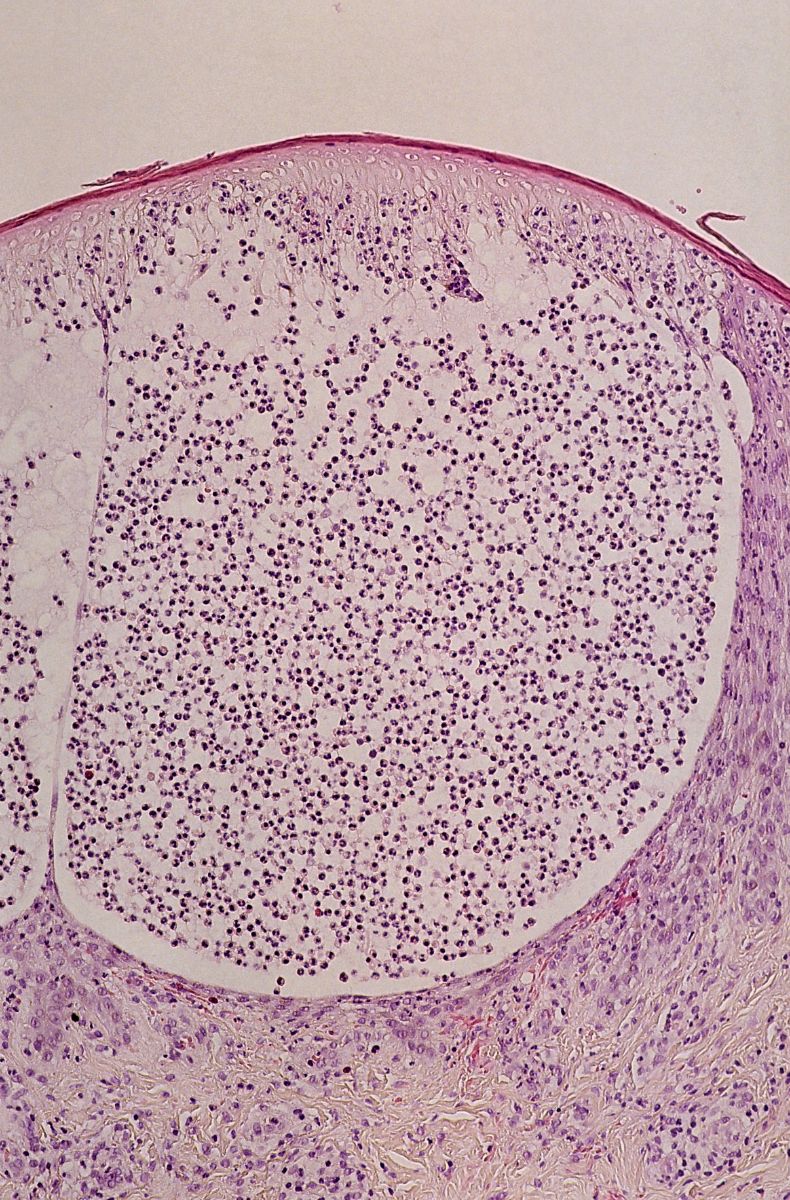

De symptomen van een chemische brandwond zijn afhankelijk van de chemische stof, de duur van contact met de stof, of het werd ingeademd of ingeslikt, of de huid intact was, de locatie van het contact, de hoeveelheid product, de concentratie van het product, en de vorm (gas, vloeistof of vaste stof). De huid kan afsterven, zwart of grijs verkleuren, roodheid of blaren vertonen, gezwollen en pijnlijk zijn. Pijn kan ook ontbreken bij diepe schade. Oogletsel en blindheid kunnen ontstaan. Chemische brandwonden worden ingedeeld in graden, waarbij het zelfde systeem als bij brandwonden wordt gebruikt. De ernst wordt bepaald door de diepte en de grootte van het aangedane oppervlak. Bij inslikken kunnen er nog extra problemen zijn zoals onregelmatige hartslag, lage bloeddruk, hartstilstand (hartaanval), zwaktegevoel of duizelig gevoel, kortademigheid of hoesten, hoofdpijn, convulsies, spiertrekkingen.